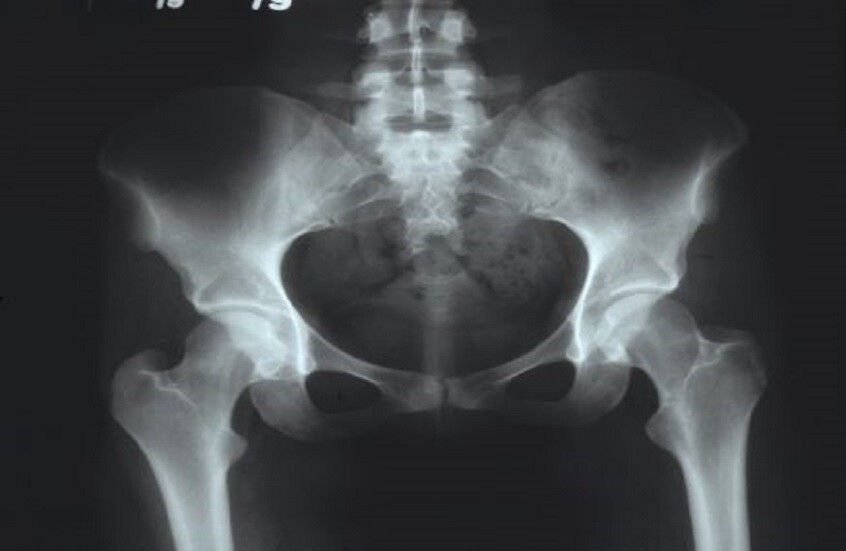

يوضح الدكتور أوليغ ساجنيكوف، أخصائي جراحة العظام، كيفية ظهور التهاب مفصل الورك، وما إذا كانت هناك سبل للوقاية من هذا المرض، ومن هم الأكثر عرضة للإصابة به.